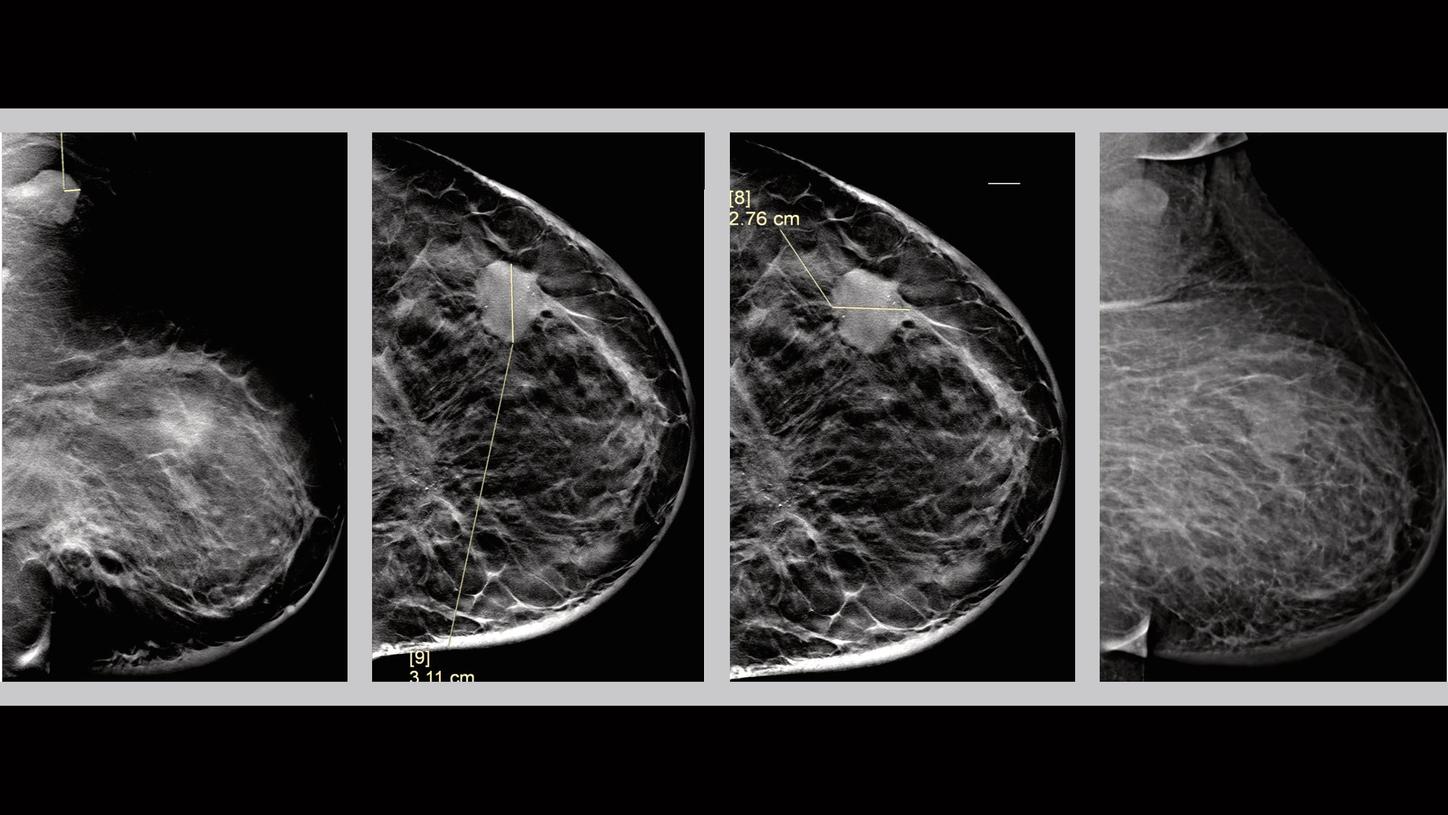

Clinical Evidence – Tomosynthesis - Case 1

History

Patient is 63 years old presented for a bilateral diagnostic mammography. The results showed palpable left breast mass and pathologically enlarged left axillary lymph nodes.

Tomosynthesis Mammography Findings

Finding 1

There is a high density, irregularly bordered mass measuring 3 cm with speculated margins seen in the middle third of the left breast upper outer quadrant (1 o’clock position), located 8 cm away from the nipple. Irregular mass correlates to the clinically palpable area. There are indeterminate calcifications with grouped distribution within the mass.

Finding 2

There is an area of architectural distortion with associated mass, best visualized through tomosynthesis images. It is seen at the posterior aspect of the left breast, lower inner quadrant, measuring 3 cm, and located 10 cm from the left nipple. There are fine linear branching calcifications within this area also best visualized by tomosynthesis images. Finding 2 is 8 cm posterior to finding 1 (the index lesion). Localized overlying skin thickening is noted at the lower central part of the left breast.

Finding 3

Pathologically enlarged left axillary lymph nodes. Cortical thickness reaching 0.6 cm.